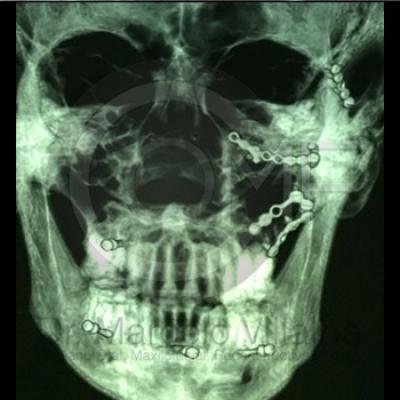

Fractura de Malar